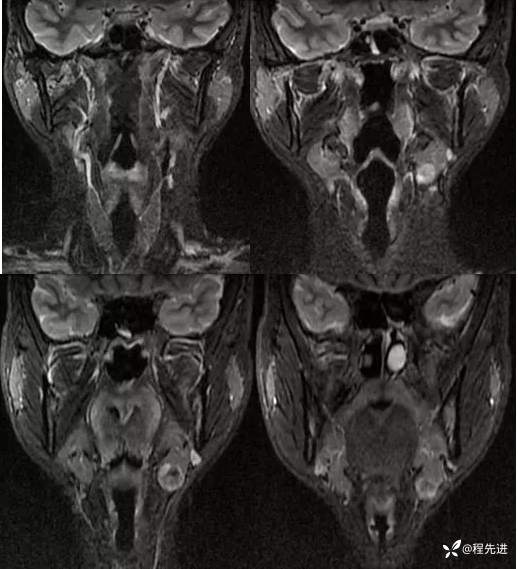

【患者信息】:男,21岁

【现病史及既往史】:发现左颌肿物2周

体格检查:左颌下触及肿物,约1.5*1.5cm,质硬,活动好

T1:

T2压脂: